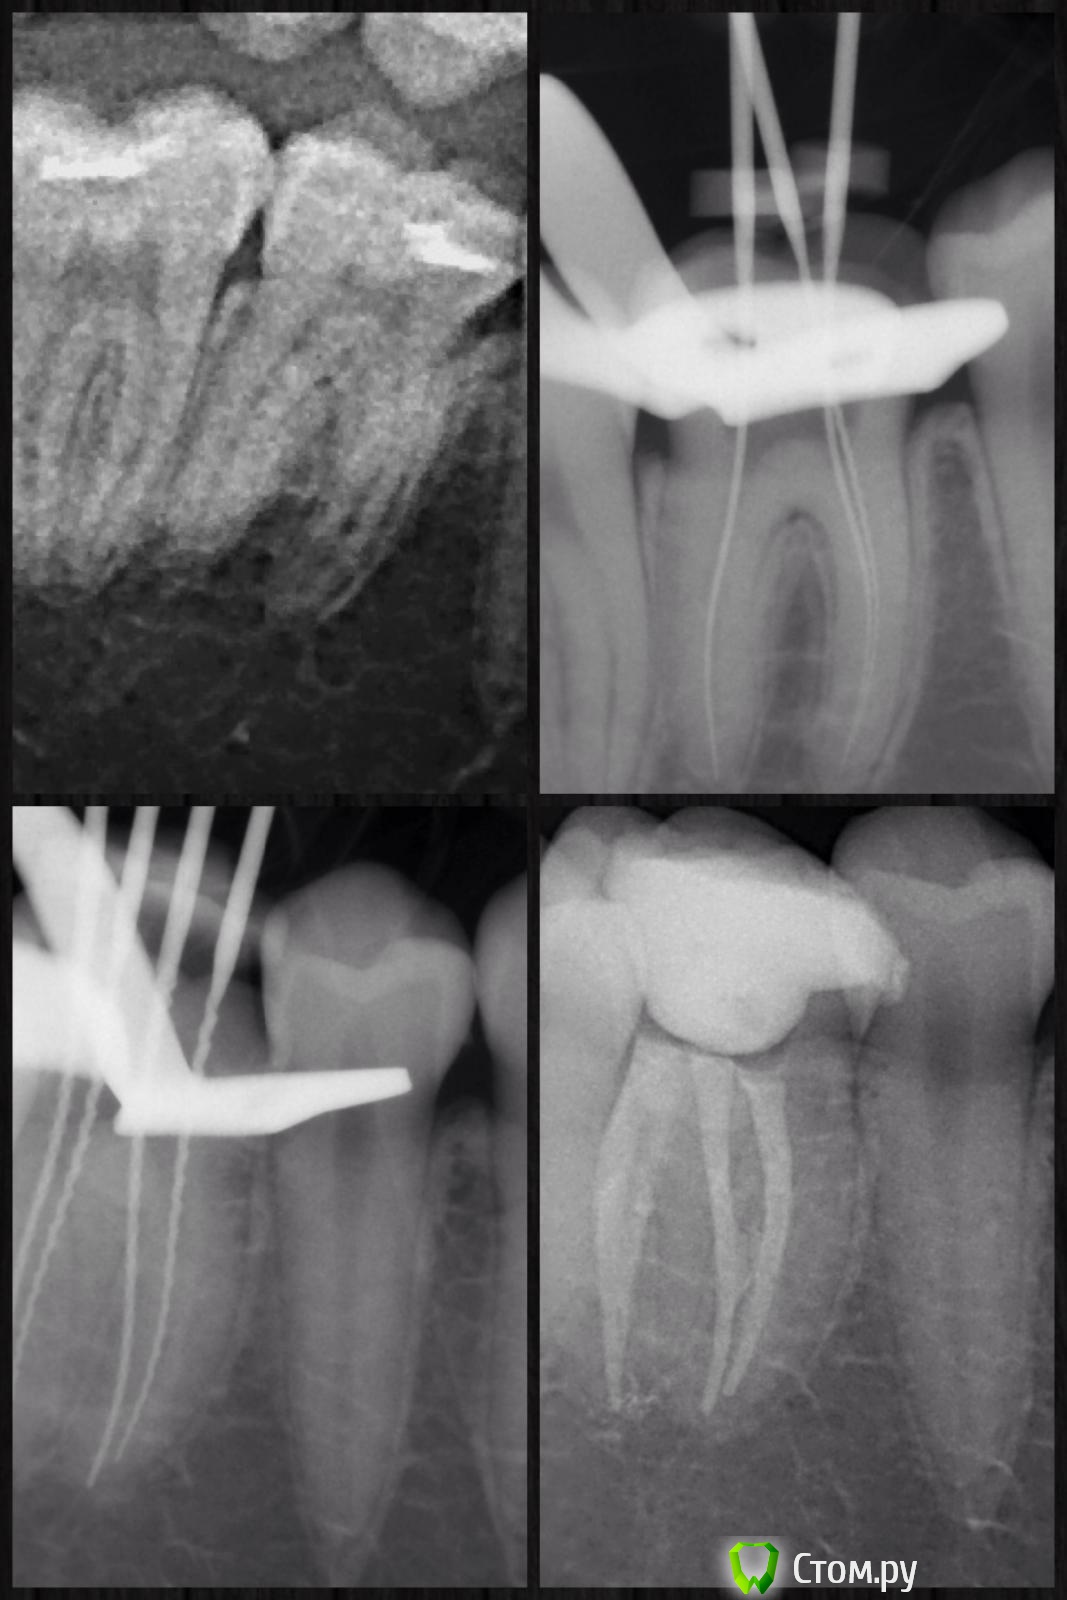

Ta.to4ka Опубликовано 20 февраля, 2014 Автор Поделиться Опубликовано 20 февраля, 2014 Ну вот коллеги первый опыт применения гуттакора.....ощущения прямо скажу неоднозначные..вводится в к/к без каких либо усилий, очень мягкий, только нет удовлетворенности в трёхмерной обтурации. Не знаю понятно ли написала. Хочется еще чем нибудь дообтурировать :-) Ссылка на комментарий